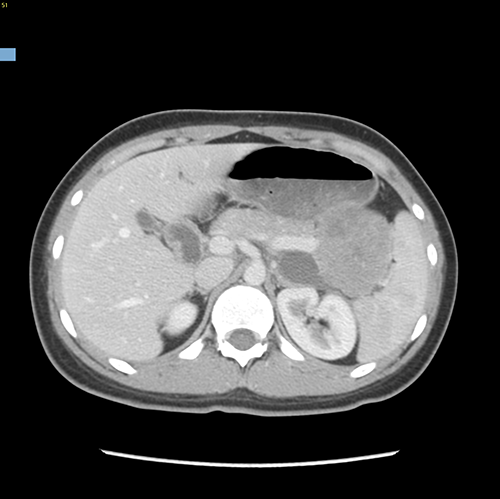

胰体尾实性假乳头状瘤---腹腔镜胰体脾切除